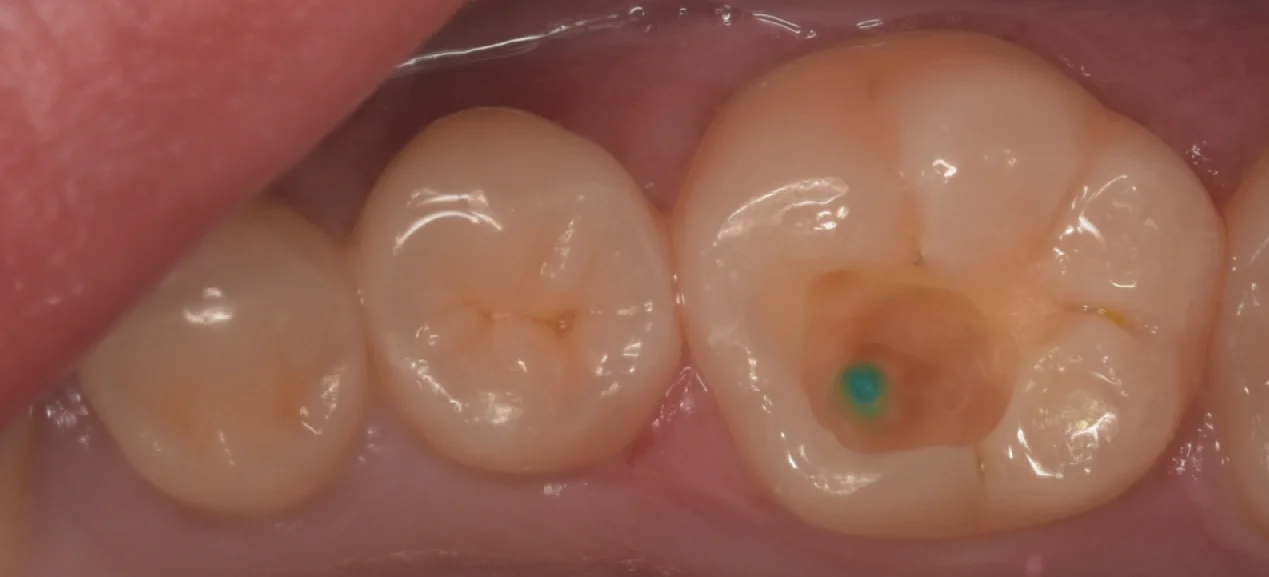

麻酔の効きが不十分だったため、う蝕検知液(虫歯かどうか色をつけて判断しやすくする薬)を使ってチマチマと削って行っていたのですが・・・

通常はだんだん薄く少なくなっていくのですが、ある一定ラインを超えた付近で一気に濃くなった場所が出ました。

実はこう言うところはもうひと削りすると神経が露出するスポットになります。

私のいつもの術式であればこう言うところも完全に除去し、露出した神経はVPTと言って神経を切断して保存する手法を取るのですが・・・

なにせ今回は麻酔の効きが不十分で痛みがでている状態でした。

この状態で削って神経を露出させるのは個人的にはもはや拷問と同義だと思ってますので、

虫歯を残したまま最終修復を行う「シールドレストレーション」を行うこととしました。

リンク先でも書いていますが、基本的に私はシールドレストレーションについては否定的なのですが、患者の痛みを我慢させてまで自分の考えを押し通すのは好きではないので、よく言えば臨機応変に対応します(笑)

エナメル・象牙ともに1mmずつの健全歯質の厚みを確保する+次亜塩素酸ナトリウム水溶液+アクセルにてそれぞれ30秒ずつ処理をして接着操作に入ります。

今回はまさにその処理を行ってから、いつも通り充填を行なっていきました。